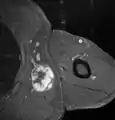

Histopathology of liposarcomas

Fig. 1 Micrograph of bone formation in a liposarcoma tumor

Fig. 7 MRI of myxoid liposarcoma of high grade, in the left axillary region of 40-year-old man, highlighted by its white color, in this horizontal section of the tumor.